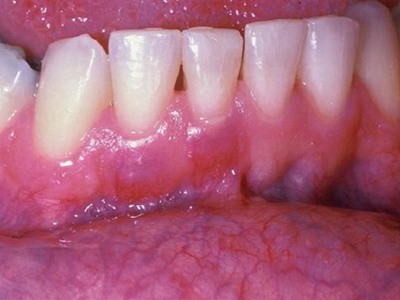

牙龈炎是发生于牙龈组织的炎症,患者可出现牙龈出血伴肿胀、发红、正常形态改变和偶尔不适等症状。本病主要由口腔卫生状况差导致,包括口腔不洁、牙菌斑等,诊断依据临床检查,治疗包括专业牙齿清洁和加强家庭口腔卫生。

牙龈炎可先引起牙齿与牙龈之间的沟(龈沟)加深,然后牙龈充血,炎症围绕一个或多个牙齿,伴牙龈乳头肿胀和易出血。一般无痛,可自行消退,也可维持轻度炎症数年。

牙龈炎常见的病因是口腔卫生差,不良的口腔卫生使牙菌斑沉积于牙齿与牙龈之间,造成龈沟加深,另外牙结石、不良修复体等也可造成牙龈炎的发生。